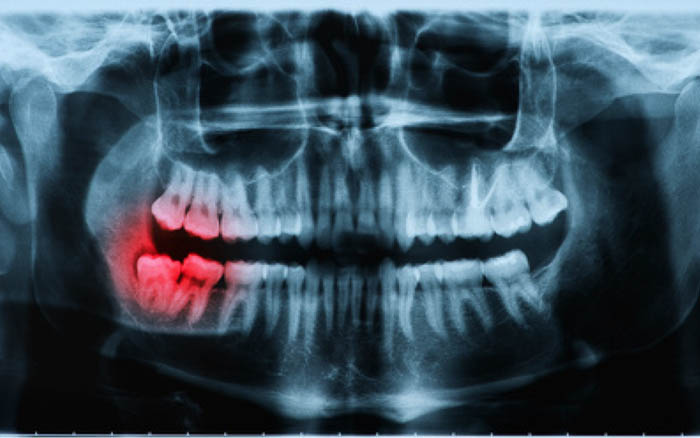

Hình ảnh chụp X-quang răng số 8